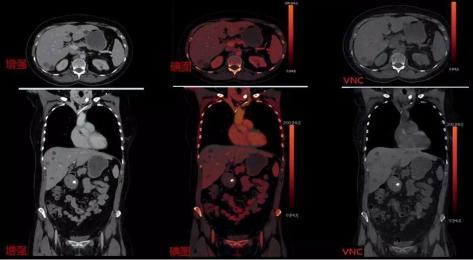

CT发展方向为从宏观的组织形态学诊断到微观组织成分分析。西门子独创采用双源双能量成像技术,同时具备4档电压组合:70/Sn150,80/Sn150,90/Sn150,100/Sn150,可根据扫描部位更合理选择电压组合,因此可以做到更精准,更绿色,是业内唯一可用于儿童的双能量成像。

双能量增强扫描可一次性获得常规增强图像、碘图及VNC4.低